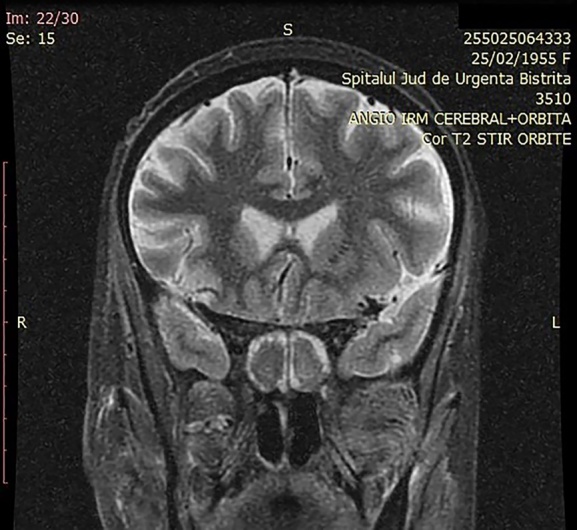

犀牛毒素粘孢子菌病是一种急性侵袭性真菌感染,临床上很少见,多发于严重免疫抑制的患者。然而,在 COVID-19 疾病患者中,粘孢子菌病的发病率急剧上升。本研究旨在讨论 COVID-19 相关粘孢子菌病患者的磁共振成像结果。本研究对 2021 年 2 月 1 日至 2021 年 10 月 30 日期间在三个耳鼻喉科住院和手术的 10 名患者进行了回顾性研究。所有患者均患有鼻腔粘液瘤病,经组织学验证,SARS-CoV-2 RT-PCR 检测呈阳性。所有患者均有鼻窦受累、鼻窦外扩散和鼻窦周围侵犯的记录。磁共振成像与术中发现之间的相关性也得到了评估。黑鼻甲征和鼻甲周围软组织浸润是粘液瘤病的早期磁共振特征。此外,磁共振成像对 COVID-19 相关粘液瘤病的术中发现具有很高的阳性预测价值。

Rhino-sinusal mucormycosis is an acute invasive fungal infection rarely encountered in the clinical setting, occurring in severe immunosuppressed patients. However, in patients suffering from COVID-19 disease a dramatic increase in the incidence of mucormycosis has been recorded. The aim of the study is to discuss the MRI findings of patients with COVID-19 associated mucormycosis. This is a retrospective review of 10 hospitalized and operated patients in three Otolaryngologic Departments between the 1st of February 2021 and the 30th of October 2021. All patients presented nasal mucormycosis, histologically verified along with documented SARS-CoV-2 positive RT-PCR test. The sinus involvement, extra sinus spread and peri-sinus invasion were documented in all patients. The correlation between MRI and intra-operative findings was also assessed. The black turbinate sign and peri-antral soft tissue infiltration are early MRI signs characteristic of mucormycosis. Moreoever, MRI has a significantly high positive predictive value for intra-operative findings in COVID-19 associated mucormycosis.